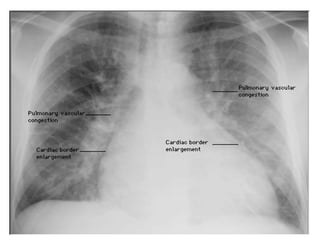

Kerley B lines

Obvious !

Pulmonary edema